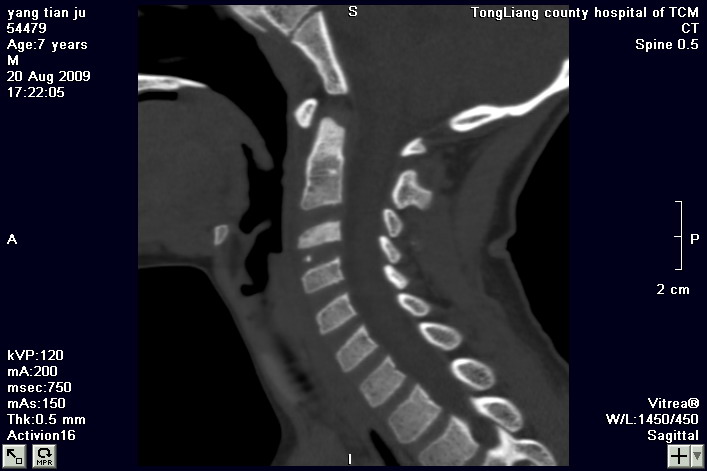

标题: PED2853:颈3/4椎间盘内高密度钙化灶,请各位会诊. [打印本页]

标题: PED2853:颈3/4椎间盘内高密度钙化灶,请各位会诊.

患儿,7岁,颈部疼痛3天,颈部活动受限.

本例应该是典型的儿童钙化性椎间盘病。

儿童钙化性椎间盘病发病年龄多在5~12岁,男女比例相当,大多数患儿发病主要表现为颈部疼痛,伴活动受限。少数有吞咽不适或肢体瘫痪。有一部分患儿无症状,是在其它检查时发现。病因尚不完全明了,可能的有:1、感染。2外伤。

儿童颈椎椎间盘钙化系一良性自限性疾病,可见于颈、胸、腰椎,以颈椎为多发,腰椎少见,多为单发。钙化位于髓核,也可累及软骨板和纤维环引起钙化主要发生于c 4~7  的髓核位于椎间隙正中或偏后,少数向前疝出,以后部多见,呈梭状、盘状、团块状或半环状;(2)颈椎生理曲度变直,椎间隙正常或增宽;(3)相邻椎体可变扁,局部凹陷变形,椎体前下缘鸟嘴状增生,或呈钳口状改变,椎前软组织增厚及环枢椎半脱位;(4)ct可清晰显示椎间盘髓核 位置的钙化灶及经破裂的纤维环向椎管内突出。(5)mri,钙化在t1及t2加权像上均呈低信号,并可见脊髓组织内异常信号。